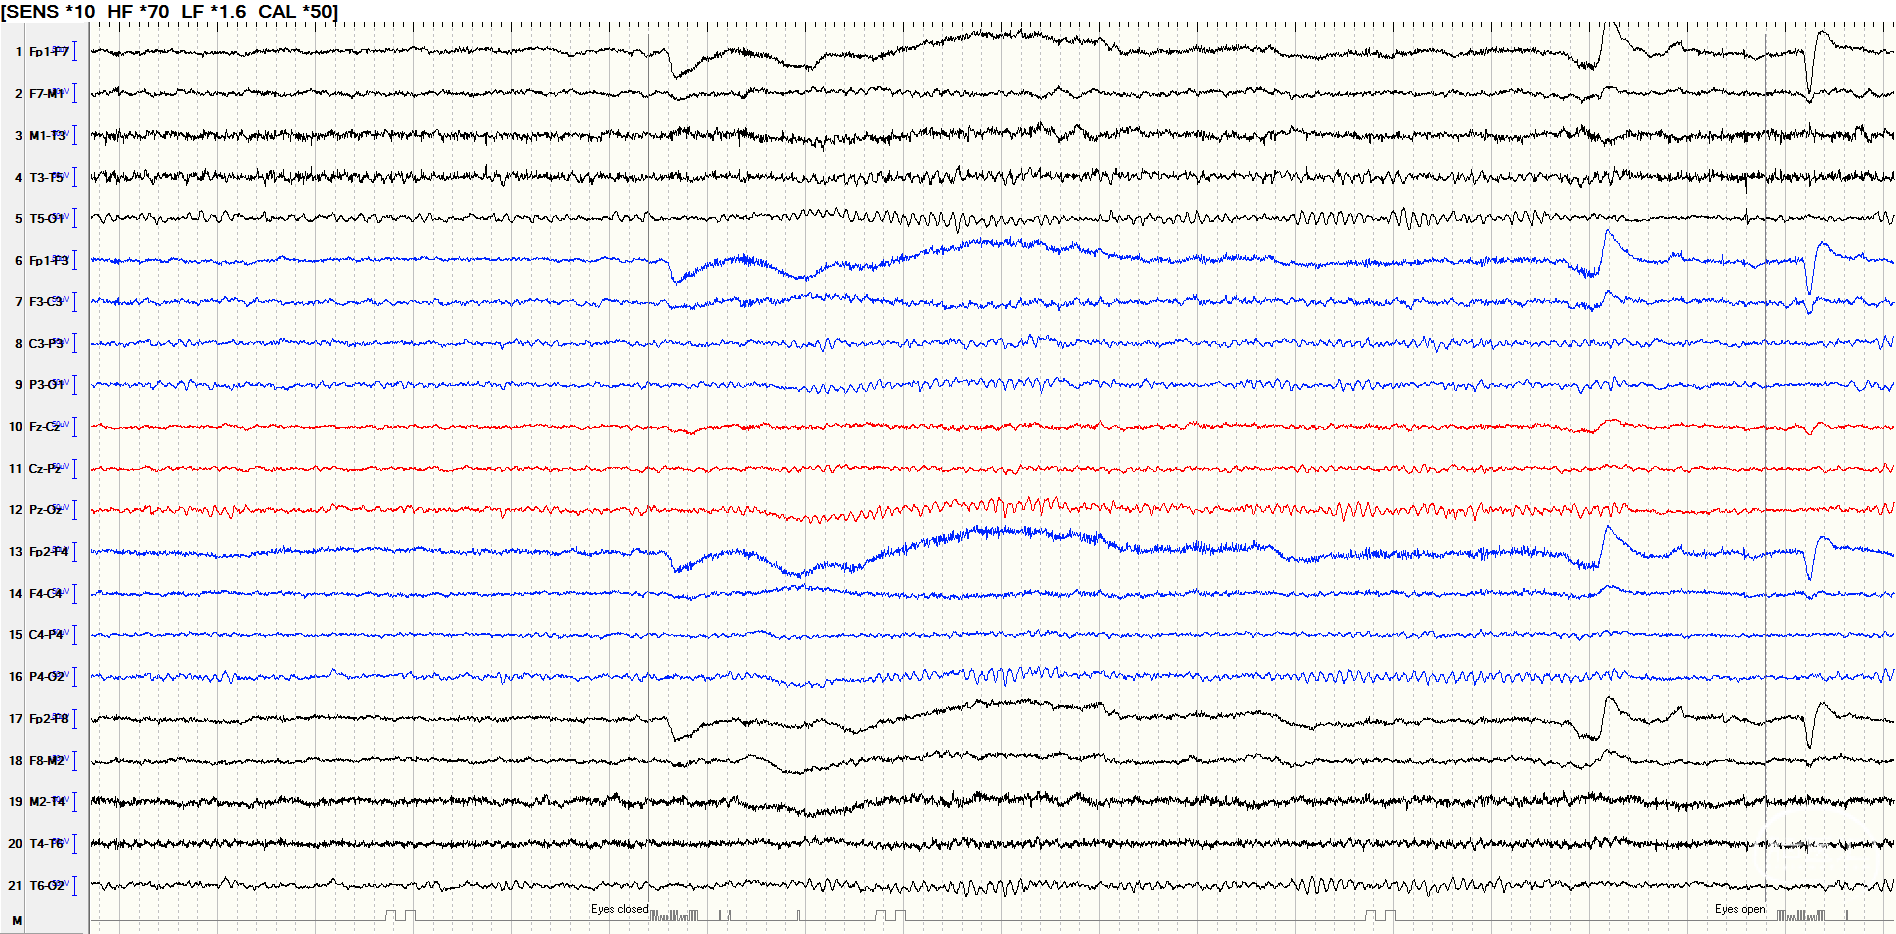

后转求至我院,详细询问病史并完善查体后发现患者脐下、右侧股外侧2*3cm色素脱失斑(图1)。完善脑电图检查提示间歇期放电脑区性,左后头著(图2),4天共监测到3次临床发作,表现为先兆(右肩重压过电感)→强直发作(累及右上肢)→阵挛发作(右上肢远端),同步脑电图示弥漫性电压低减,无侧向性(图3)。头颅MRI提示颅内多发异常信号(图4)。头颅CT提示颅内有钙化灶(图5)。头颅PET见左侧楔前叶低代谢(图6)。

图2.间歇期放电脑区性,脑区性,左后头著。

图3.发作期脑电图示弥漫性电压低减,无侧向性。